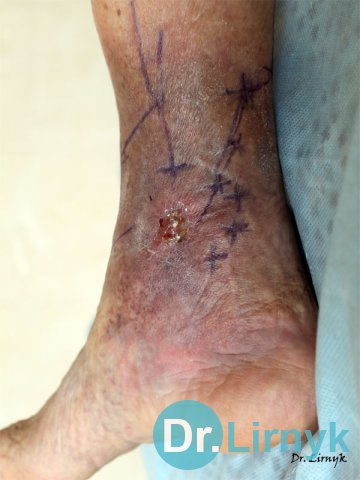

Wynik leczenia wrzodu troficznego w naszej klinice.

Partycjonowanie przed operacją

Wrzód troficzny. Wrzód nie goił się7 lat. Nieudana próba przeniesienia skóry. Pacjentowi 76 lat.